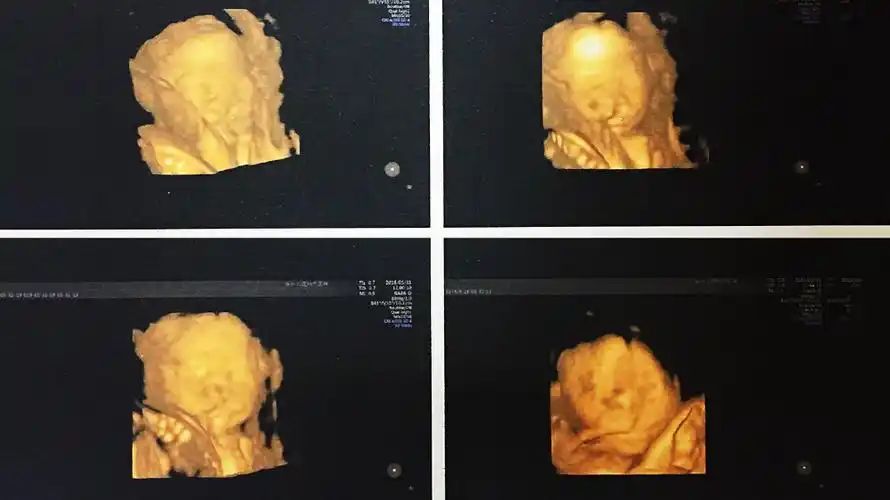

四维照来了

1.2三维超声显示单侧唇裂.

四维的图片能不能看出唇裂呢?

小伙伴们我前几天做四维得出胎儿唇裂怎么办

(单侧唇裂)

夫妻俩都很高兴,然而,22周的时候,做大排畸检查,医生说宝宝唇裂,建议

想知道宝宝是否健康 超声影像(四维彩超) 针对22—28周之间的宝妈